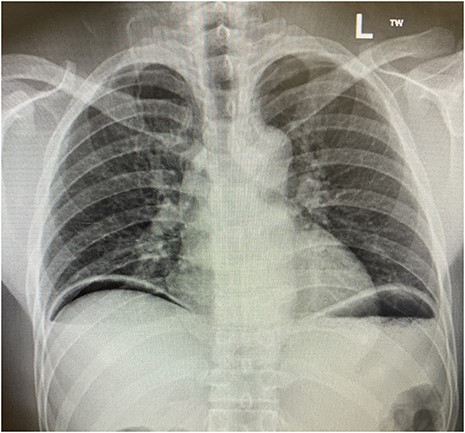

The patient was transferred to the surgical ward for ongoing cares, remaining nil by mouth and commenced on intravenous antibiotics and proton pump inhibitor infusion. On post-operative day 3, a follow-through contrast study showed no leak of enteric contents from the stomach (Fig. 3) with transit of the contrast into the duodenum, and a concurrent ileus was shown with prominent small bowel loops (Fig. 4). A clear fluid diet was initiated, with gradual upgrade before discharge to usual residence and follow-up gastroscopy as outpatient.